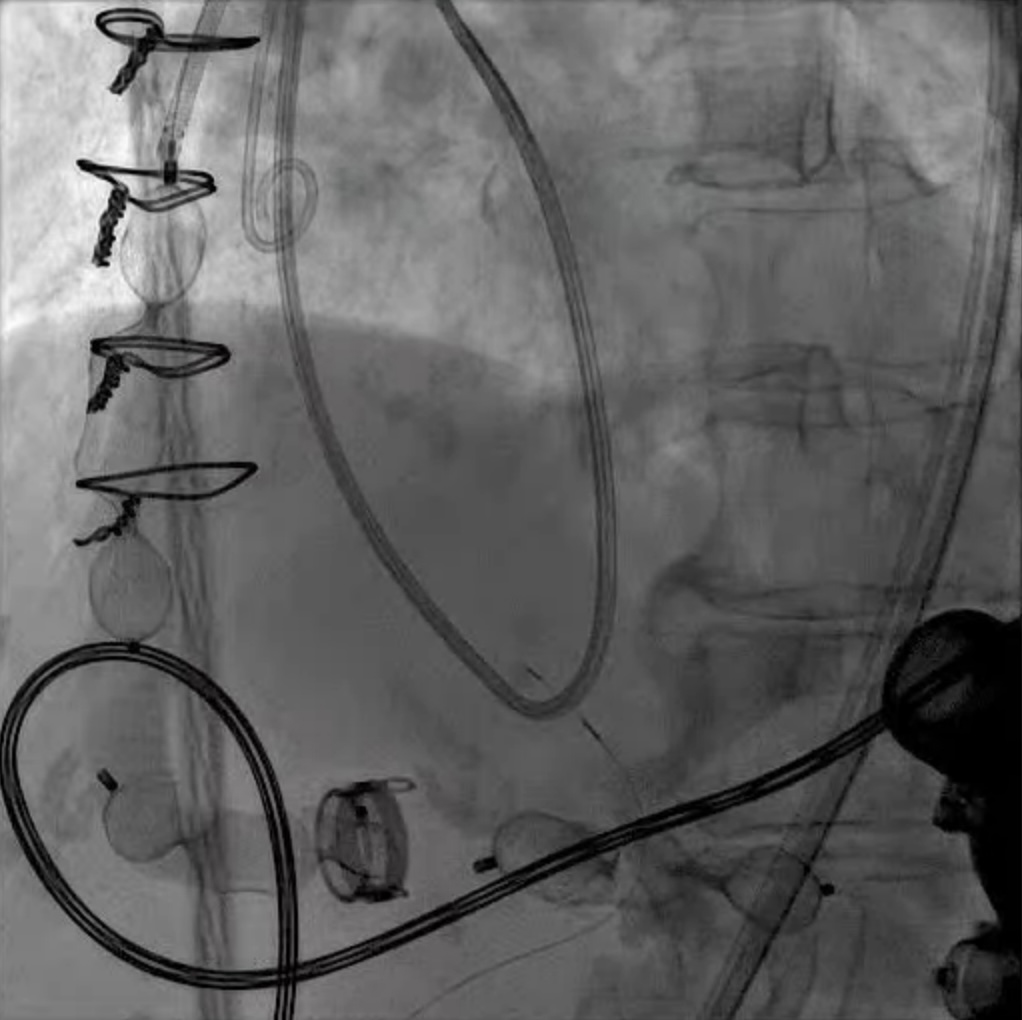

LVAD deactivation can be achieved by surgical explant via median sternotomy or via a hybrid surgical/percutaneous approach described as decommissioning [37]. Complete explant is recommended in younger patients and those with infected drivelines and/or pump. Decommissioning implies retention of the pump within the body. The driveline is cut and buried subcutaneously. The outflow cannula must be occluded to prevent closed loop regurgitant flow from the aorta into the left ventricle, typically with endovascular occlusive device/s at the OFG-ascending aorta anastomosis (Fig. 12). Surgical decommissioning can be achieved minimally invasively and without cardiopulmonary bypass.

Fig. 12. LVAD decommissioning. Outflow cannula occlusion with a series of three large Amplatzer vascular plug 2 (AVP2) from the proximal end to the distal end of the cannula.